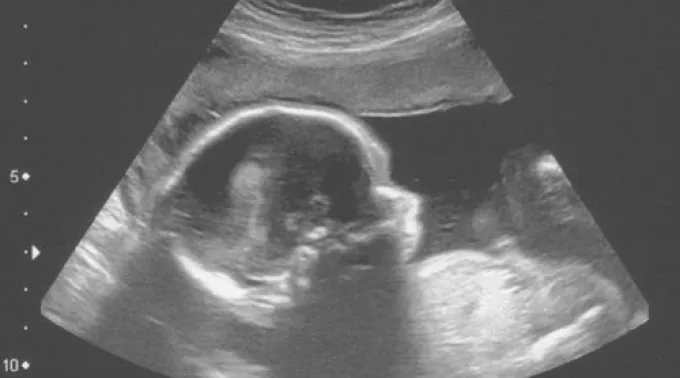

Hoje, 25 de março, diversos países do mundo celebram o Dia do Nascituro, que tem por objetivo comemorar, promover e defender a vida humana desde a concepção no ventre da mãe.